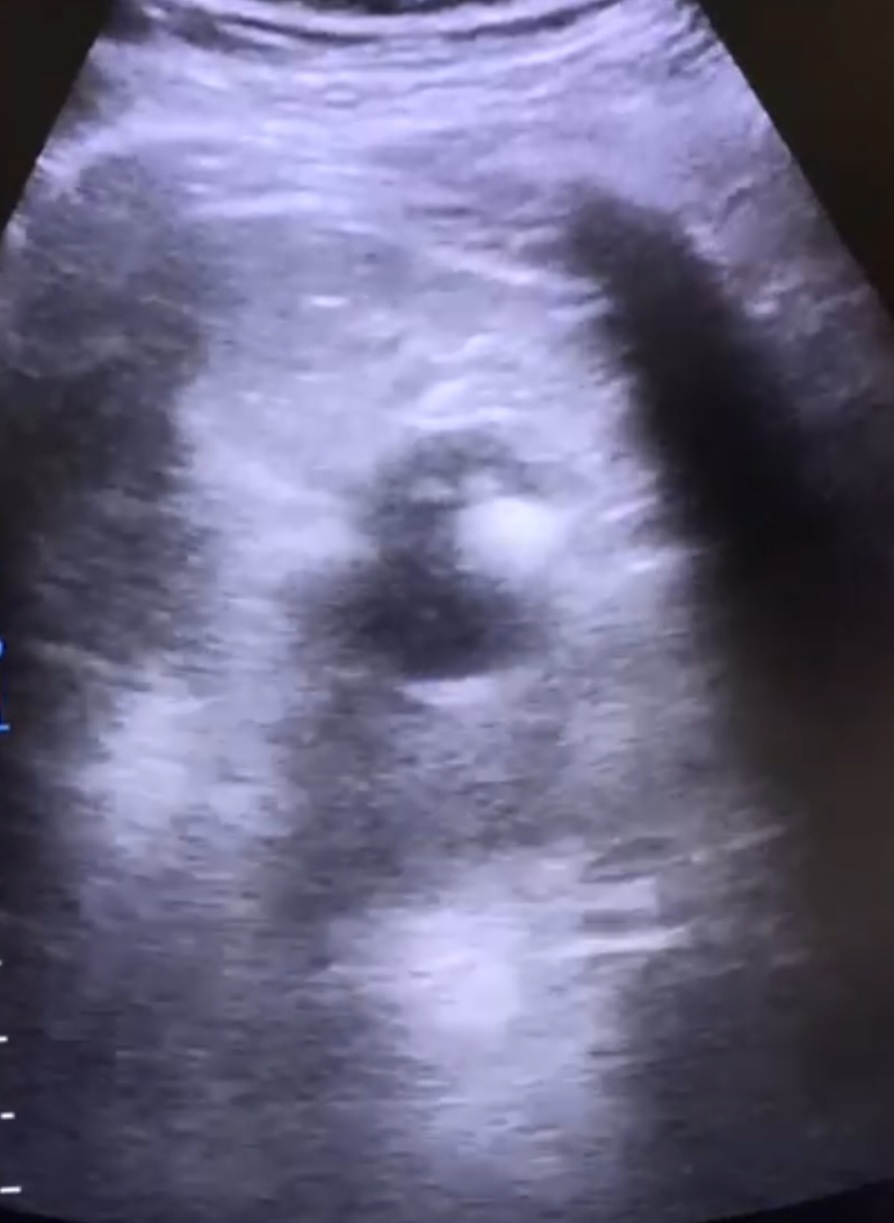

Se deriva a SUH: ID de hernia inguinal no complicada, se cita en consulta externa con cirugía; se realiza ecografía de partes blandas y se descarta la presencia de hernias. Por persistencia de síntomas acude en varias ocasiones a AP; como hallazgos casual test de aliento positivo, se pauta TTX erradicador con posterior negativización. La clínica no cedía, pese a ttx analgésico intercalado, y se acentuó en FID por lo que vuelve a consultar por su MAP y se deriva a SUH con ID de apendicitis/ hernia inguinal/orquitis; con ID de epididimitis se le pauta ATB por 7 días + urocultivo negativo. En AP se solicita cita para urología. Se le vuelve a remitir en otra ocasión desde AP a SUH: ID de dolor abdominal inespecífico y remite a su MAP. ECOABD en su MAP: imagen quística en polo superior renal izquierdo, solicita ECOABD reglada: imagen en la cara lateral del polo superior del riñón izquierdo de características quísticas de 3x2 cm, con imágenes ecogénicas en su interior con sombra acústica y con artefacto en cola de cometa (sugiere naturaleza cálcica).

Se solicita TAC para mejor valoración: Quiste en polo superior del riñón izquierdo, con leche cálcica en interior, que comunica con el sistema excretor.